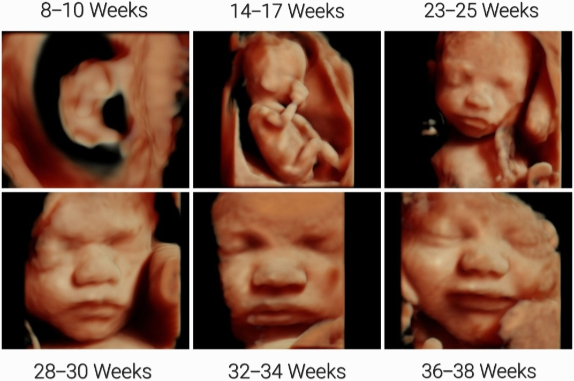

- 20 – 23 tuần 6 ngày: Siêu âm 4 chiều và xét nghiệm nước tiểu

Hình 3. Siêu âm 4 chiều.